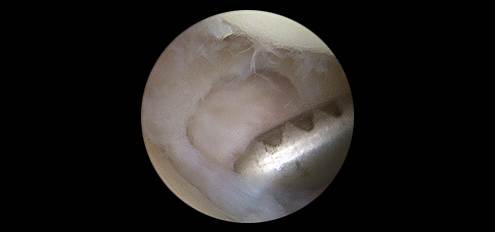

척골과 수근골 사이에 있는 연골인

삼각섬유연골의 손상도 동반될 수 있습니다.

삼각섬유연골복합체(TFCC) 파열은 요골과 척골을 연결하는

인대조직인 TFCC가 손상되어 발생하는 질환입니다.